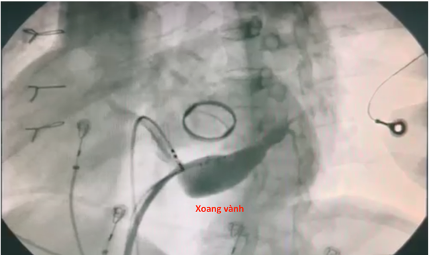

Tiến hành map vùng sau vách bên phải vòng van 3 lá ghi nhận điện thế nhĩ thất hoà vào nhau tương tự sau vách bên trái. Tiến hành cắt đốt vị trí này thì chấm dứt đường phụ nhưng sau đó tái phát lại. Tiến hành thăm dò vùng vị trí thượng mạc trong lỗ tĩnh mạch vành hướng về bên trái ghi nhận điện thế nhĩ thất hoà vào nhau làm 1, tiến hành cắt đốt vị trí này thì chấm dứt hoàn toàn đường dẫn truyền phụ này. Bệnh nhân khôi phục nhịp xoang dẫn truyền hoàn toàn qua nút nhĩ thất thông thường.

Hình: vị trí cắt đốt thành công trong xoang vành bằng catheter năng lượng cao và hình ảnh xoang vành.